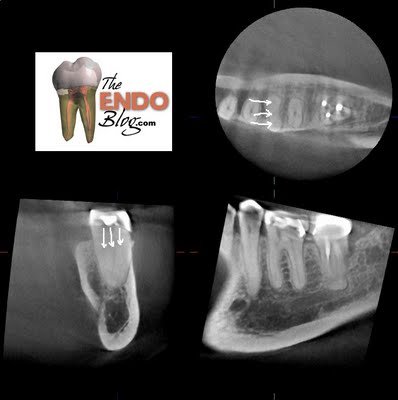

The CBCT gives us valuable information about tooth #19. For example, following CBCT, prior to starting RCT #19, we know that the mesial root is a single root with 3 canals that merge. We also know that distal root has a single canal.

3 canals found in a single, mesial root. This was identified prior to treatment with CBCT. In this particular case, the 3rd (middle) canal would likely not have been found due to its location.

In this case, the CBCT identified a variation in the mesial canal morphology. Knowing that the mesial root was a single root and that it had 3 canals, gave me the ability & confidence to explore the ML-MB groove to a greater depth than would have normally been done for fear of perforation. This is a perfect example of radiographic information that is not available through traditional 2D imaging. This information allowed us to provide better cleaning, shaping and obturation, which will lead to a better RCT.